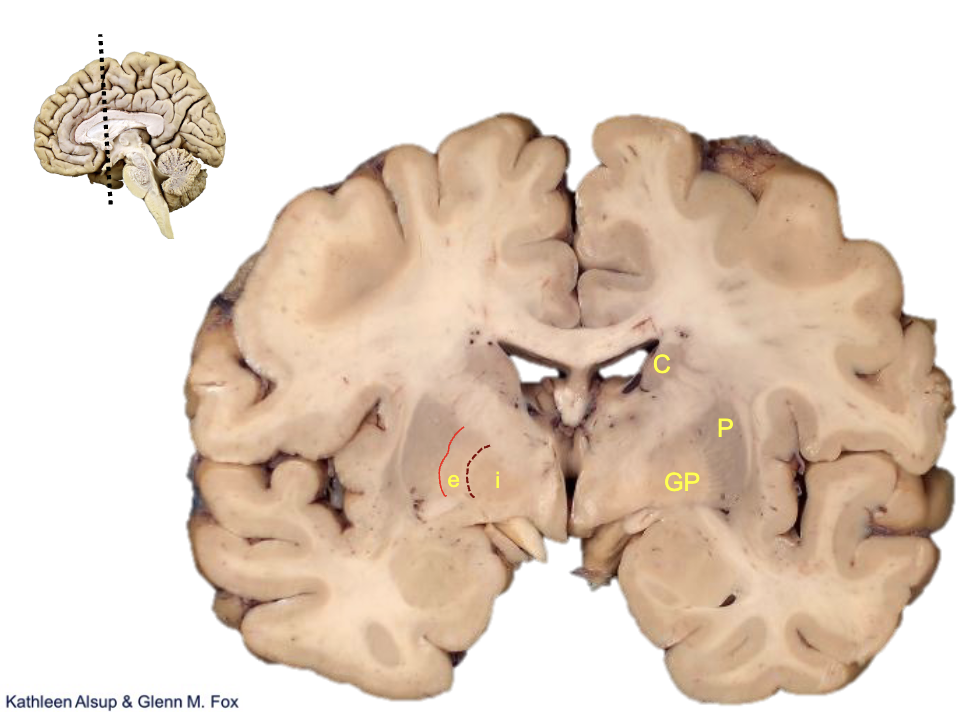

<p><strong>what is c?</strong></p>

caudate

<p><strong>what is p?</strong></p>

putamen

<p><strong>what is gp?</strong></p>

globus pallidus

<p><strong>what is i?</strong></p>

internal segment

<p><strong>what is e?</strong></p>

external segment